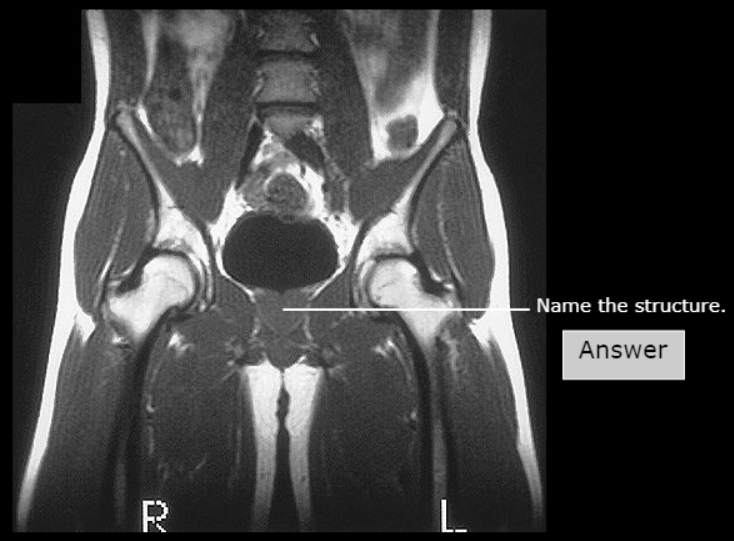

Broad Ligament of Uterus